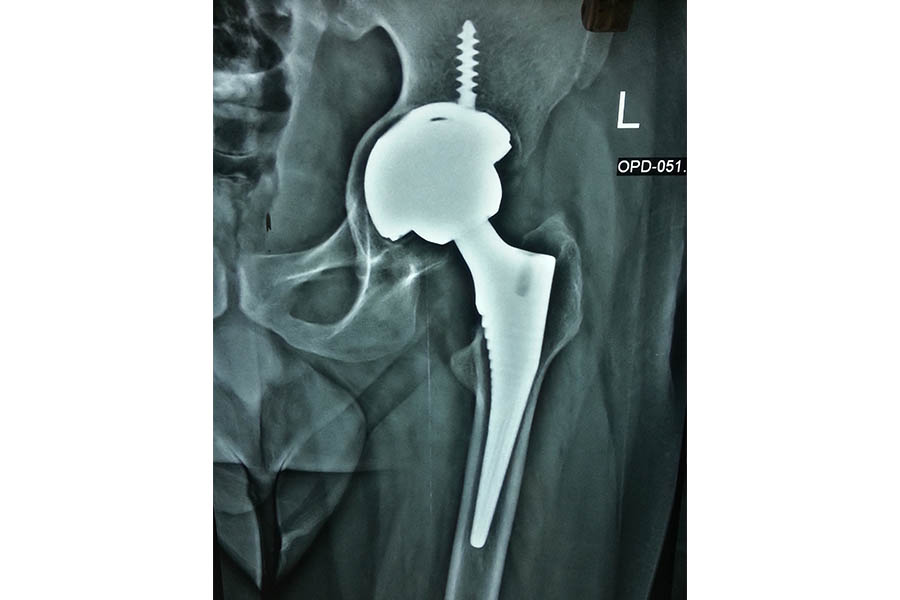

Total Hip Replacement

Case 5

Difficult Replacement

Case 1